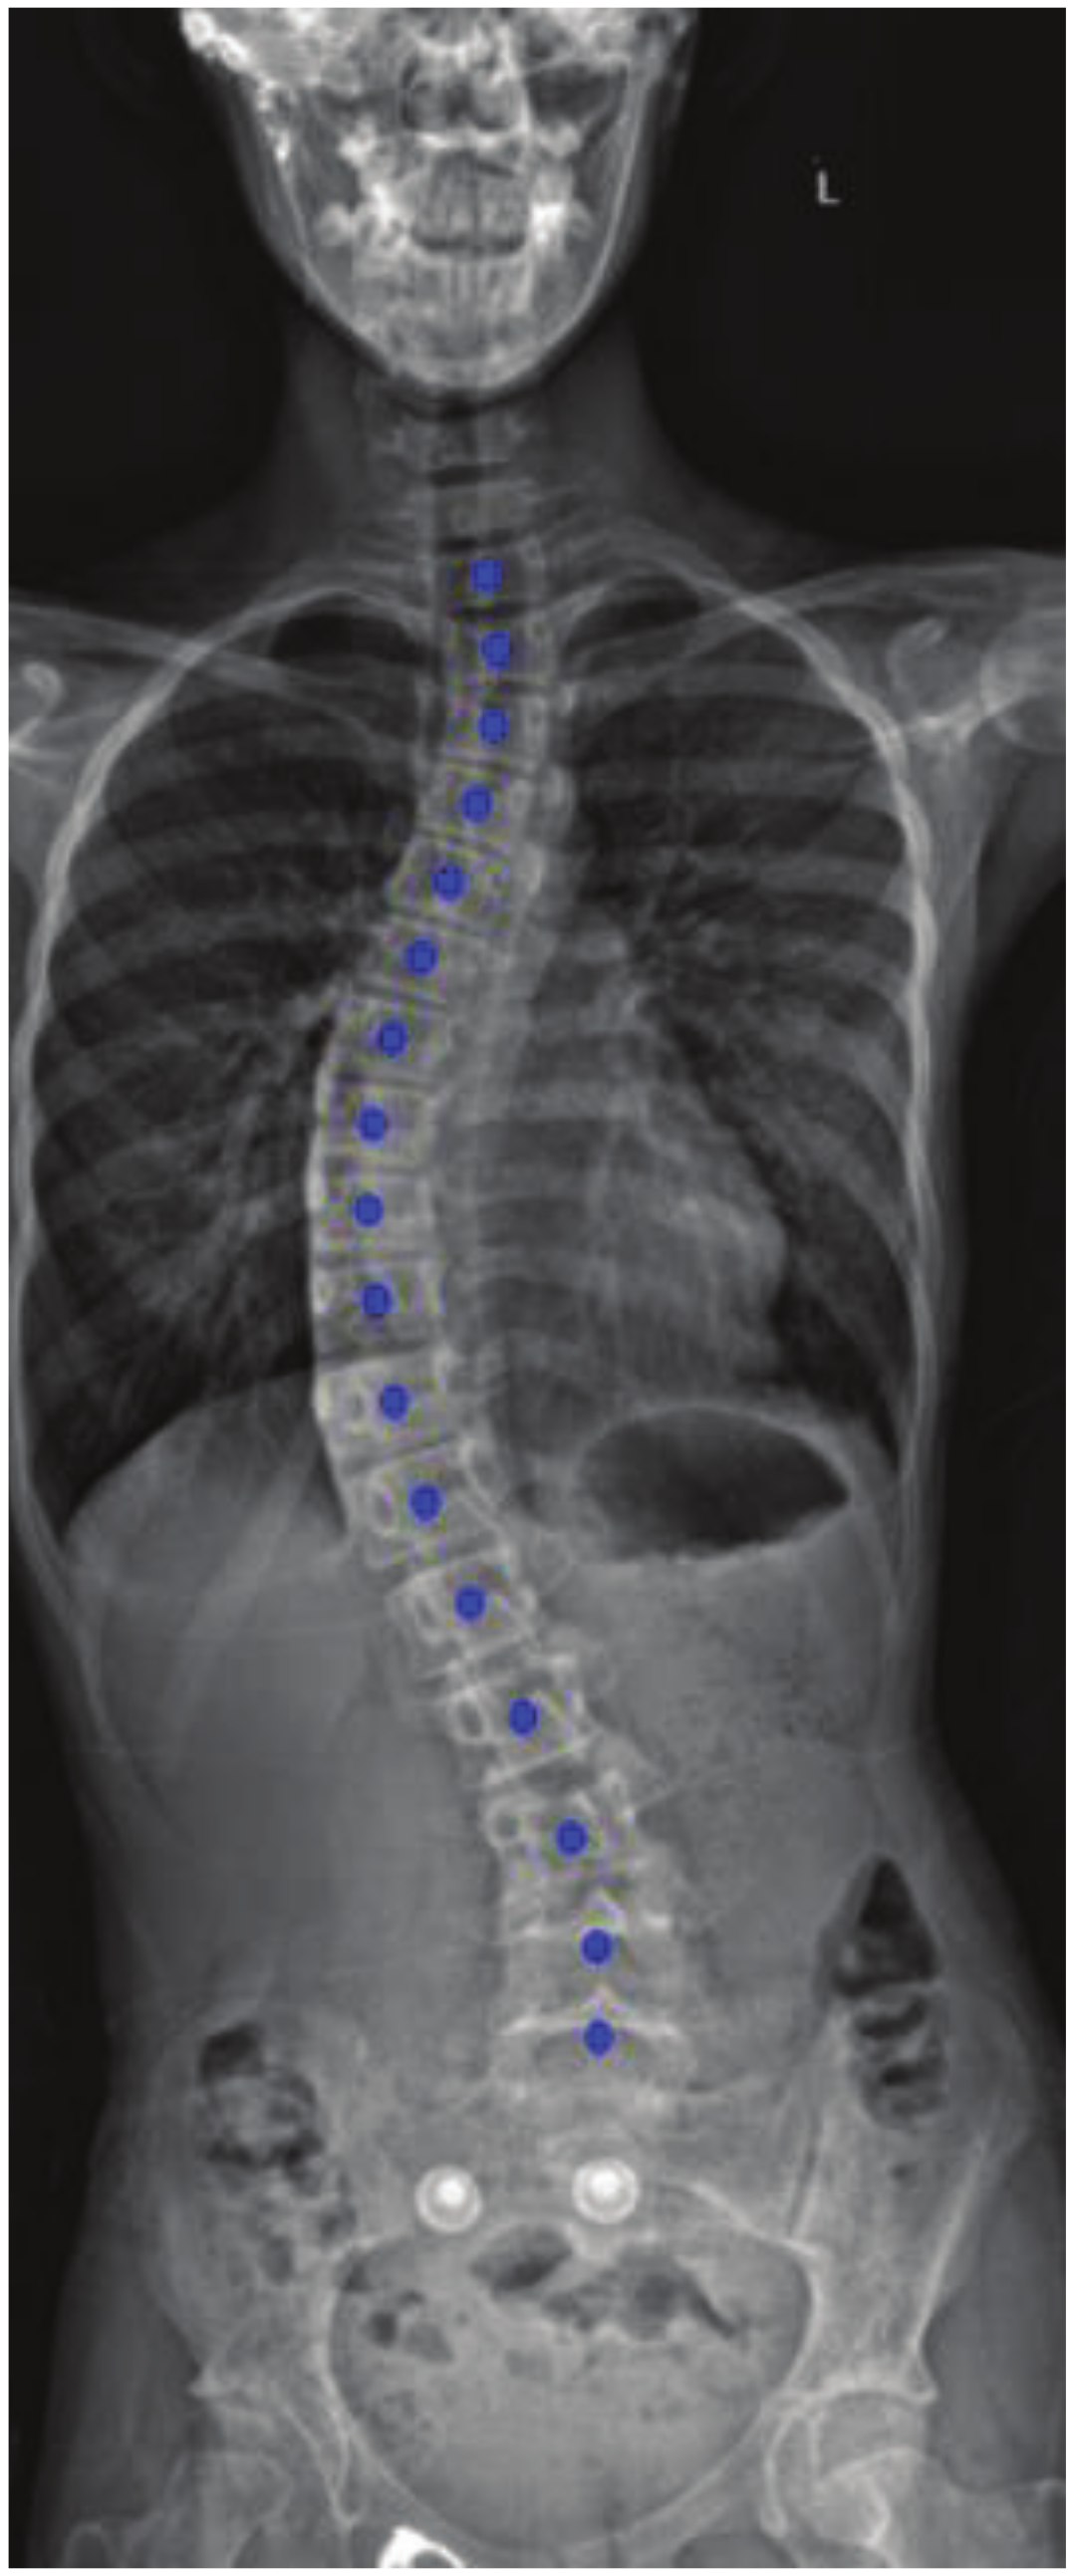

Vertebral Center Points Locating and Cobb Angle Measurement Based on Deep Learning

2. Manual Measurement of Scoliosis

3. Materials and Methods

3.4.2. Spine Curve Fitting and Cobb Angle Calculation